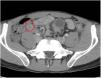

A 27-year-old man came to the emergency room due to 24h epigastric abdominal pain radiating to the right iliac fossa. Upon physical examination, the Blumberg sign was positive and laboratory test results showed leukocytosis with neutrophilia. An abdominal CT scan revealed a post-ileal appendix with thickened walls in which small diverticula were identified (fig. 1, red circle). There were inflammatory changes and a small quantity of fluid in the periappendiceal fat, alterations consistent with appendiceal diverticulitis associated with acute appendicitis. Appendectomy was performed and multiple diverticula, with microperforation in the proximal third of one of them (fig. 2, yellow arrow), were confirmed in the anatomopathologic study. Appendiceal diverticulitis is an uncommon cause of acute abdomen and is clinically indistinguishable from acute appendicitis. On occasion it can be differentiated due to a more indolent course and certain aspects of its epidemiology and progression. Although CT images can be very suggestive of the pathology, the definitive diagnosis is made through histologic study of the surgical specimen in the majority of cases.